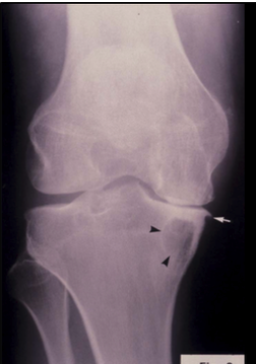

What is shown on this X-ray?

A

Subchondral cysts (Black arrows)

Osteophytes (White arrows)